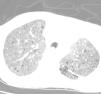

Mujer de 52 años con patrón intersticial pulmonary retraso mental profundo

52 year old woman with interstitial pulmonary pattern and severe mental retardation